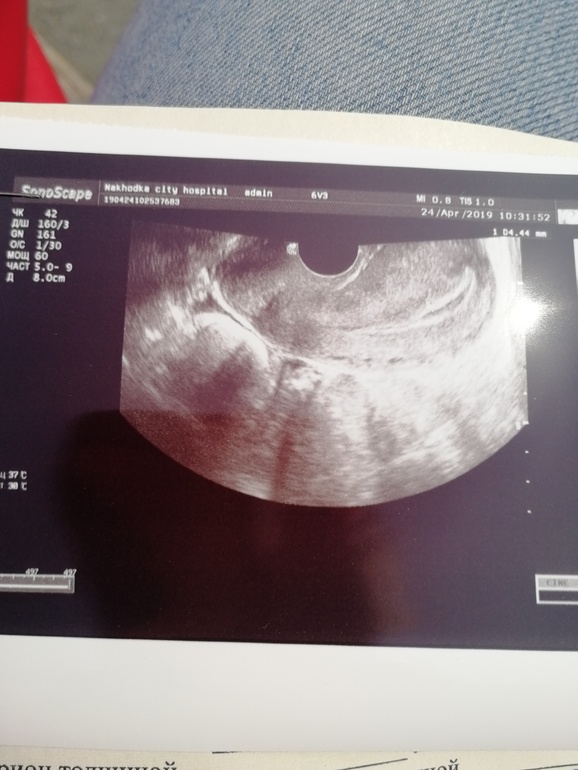

Сегодня кровотечение началось, но не алая кровь. Приехала в больницу, врач на осмотре не видит беременность. Узи ПЯ ни в матке, ни в трубе не обнаружили. Но с последнего узи матка подросла. Легла в стационар, назначили узи в динамике. Может завтра поеду сдам хгч, тут не делают.

У меня тоже какая-то жопа, извиняюсь за выражение, но по-другому не знаю как это назвать. Вчера вечером начало слегка потягивать в низу живота. Сегодня проснулась, продолжается, пошла в туалет и капец - вытираюсь и выделения начались небольшие, но были сгусточки как хлопья. Вызвала скорую, сейчас в больнице нахожусь. Сделали узи, ничего не видят, Э в матки ничего не видят, вокруг ничего не видят, внематочную тоже не видят, полнейшая неизвестность, это ужасно. ХГЧ при этом сдала вчера увеличился больше чем в два раза и сейчас он 929,96. Я вообще уже ничего не понимаю. Держите в курсе, как у вас дела.